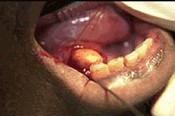

问题 男性,36岁。进食时左侧颌下区肿胀疼痛,进食后数小时方可逐渐消退。下颌下腺导管开口处红肿,轻压腺体导管口溢脓。

选项 检查见图示,以下哪项检查有助于进一步确诊 ( ) A.曲面断层片 B.下颌骨后前位片 C.下颌前部颌片 D.下颌下腺造影 E.下颌横断颌片

答案 D